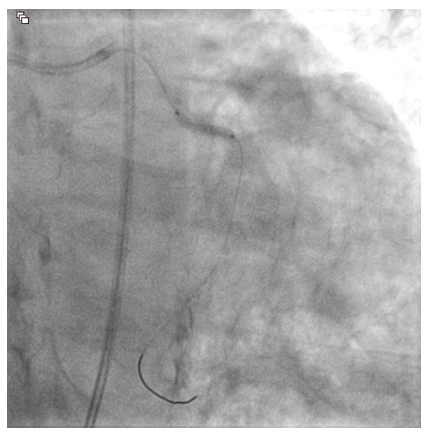

Despite this, access past the mid-portion of the lesion continued to prove difficult due to the significant angulation of the lesion. Utilizing a 6 French GuideLiner catheter (Teleflex), the 2.0 mm x 15 mm Takeru™ RX balloon was able to be advanced past the mid-portion of the circumflex lesion for additional angioplasty. Following this, IVL was performed using 60 shocks (6 inflations) of a 3.0 mm x 12 mm Shockwave lithotripsy balloon (Shockwave Medical) (Figure 4).